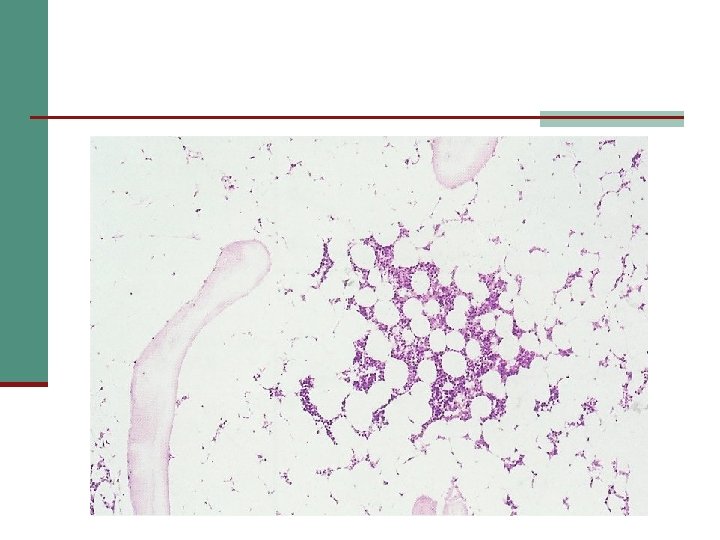

Laboratory features (cont): Bone marrow aspiration and trephine biopsy: n Hypocellularity n ↑↑ fat cells numbers n Iron stores usually increased Cytogenetic analysis: Certain abnormalities may suggest a higher risk of myelodysplasia and acute leukemia Flow cytometry: CD 56, CD 59 may be absent, indicating the presence of PNH.